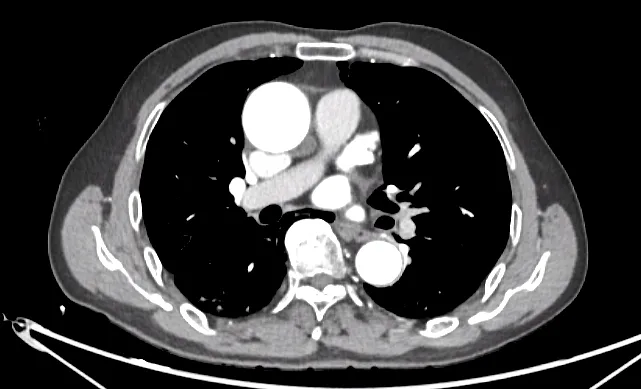

胸部CTA:主动脉根部局部稍扩张。

冠脉CTA:右冠动脉近段管壁软斑,管腔约轻度狭窄。左右冠状动脉起源及走行未见异常,整体呈右冠优势型。右冠状动脉(A)近段管壁则软斑影,管腔约轻度狭窄。左冠状动脉主干管壁未则明显异常,管腔未见狭窄。前降支(LAD)、第一对角支(D1)、第二对角支(D2)、左旋支(LCX)、第一钝缘支(OM1)、中间支(RI)、后降支(PDA)及后外侧支(PLB)未见确切斑块及狭窄征象。